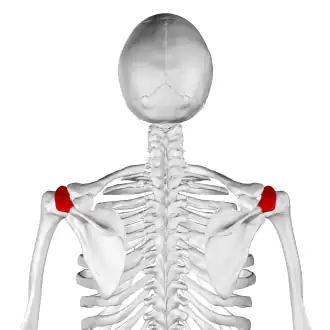

Skeleton, posterior view. Acromion of each scapula shown in red. | |